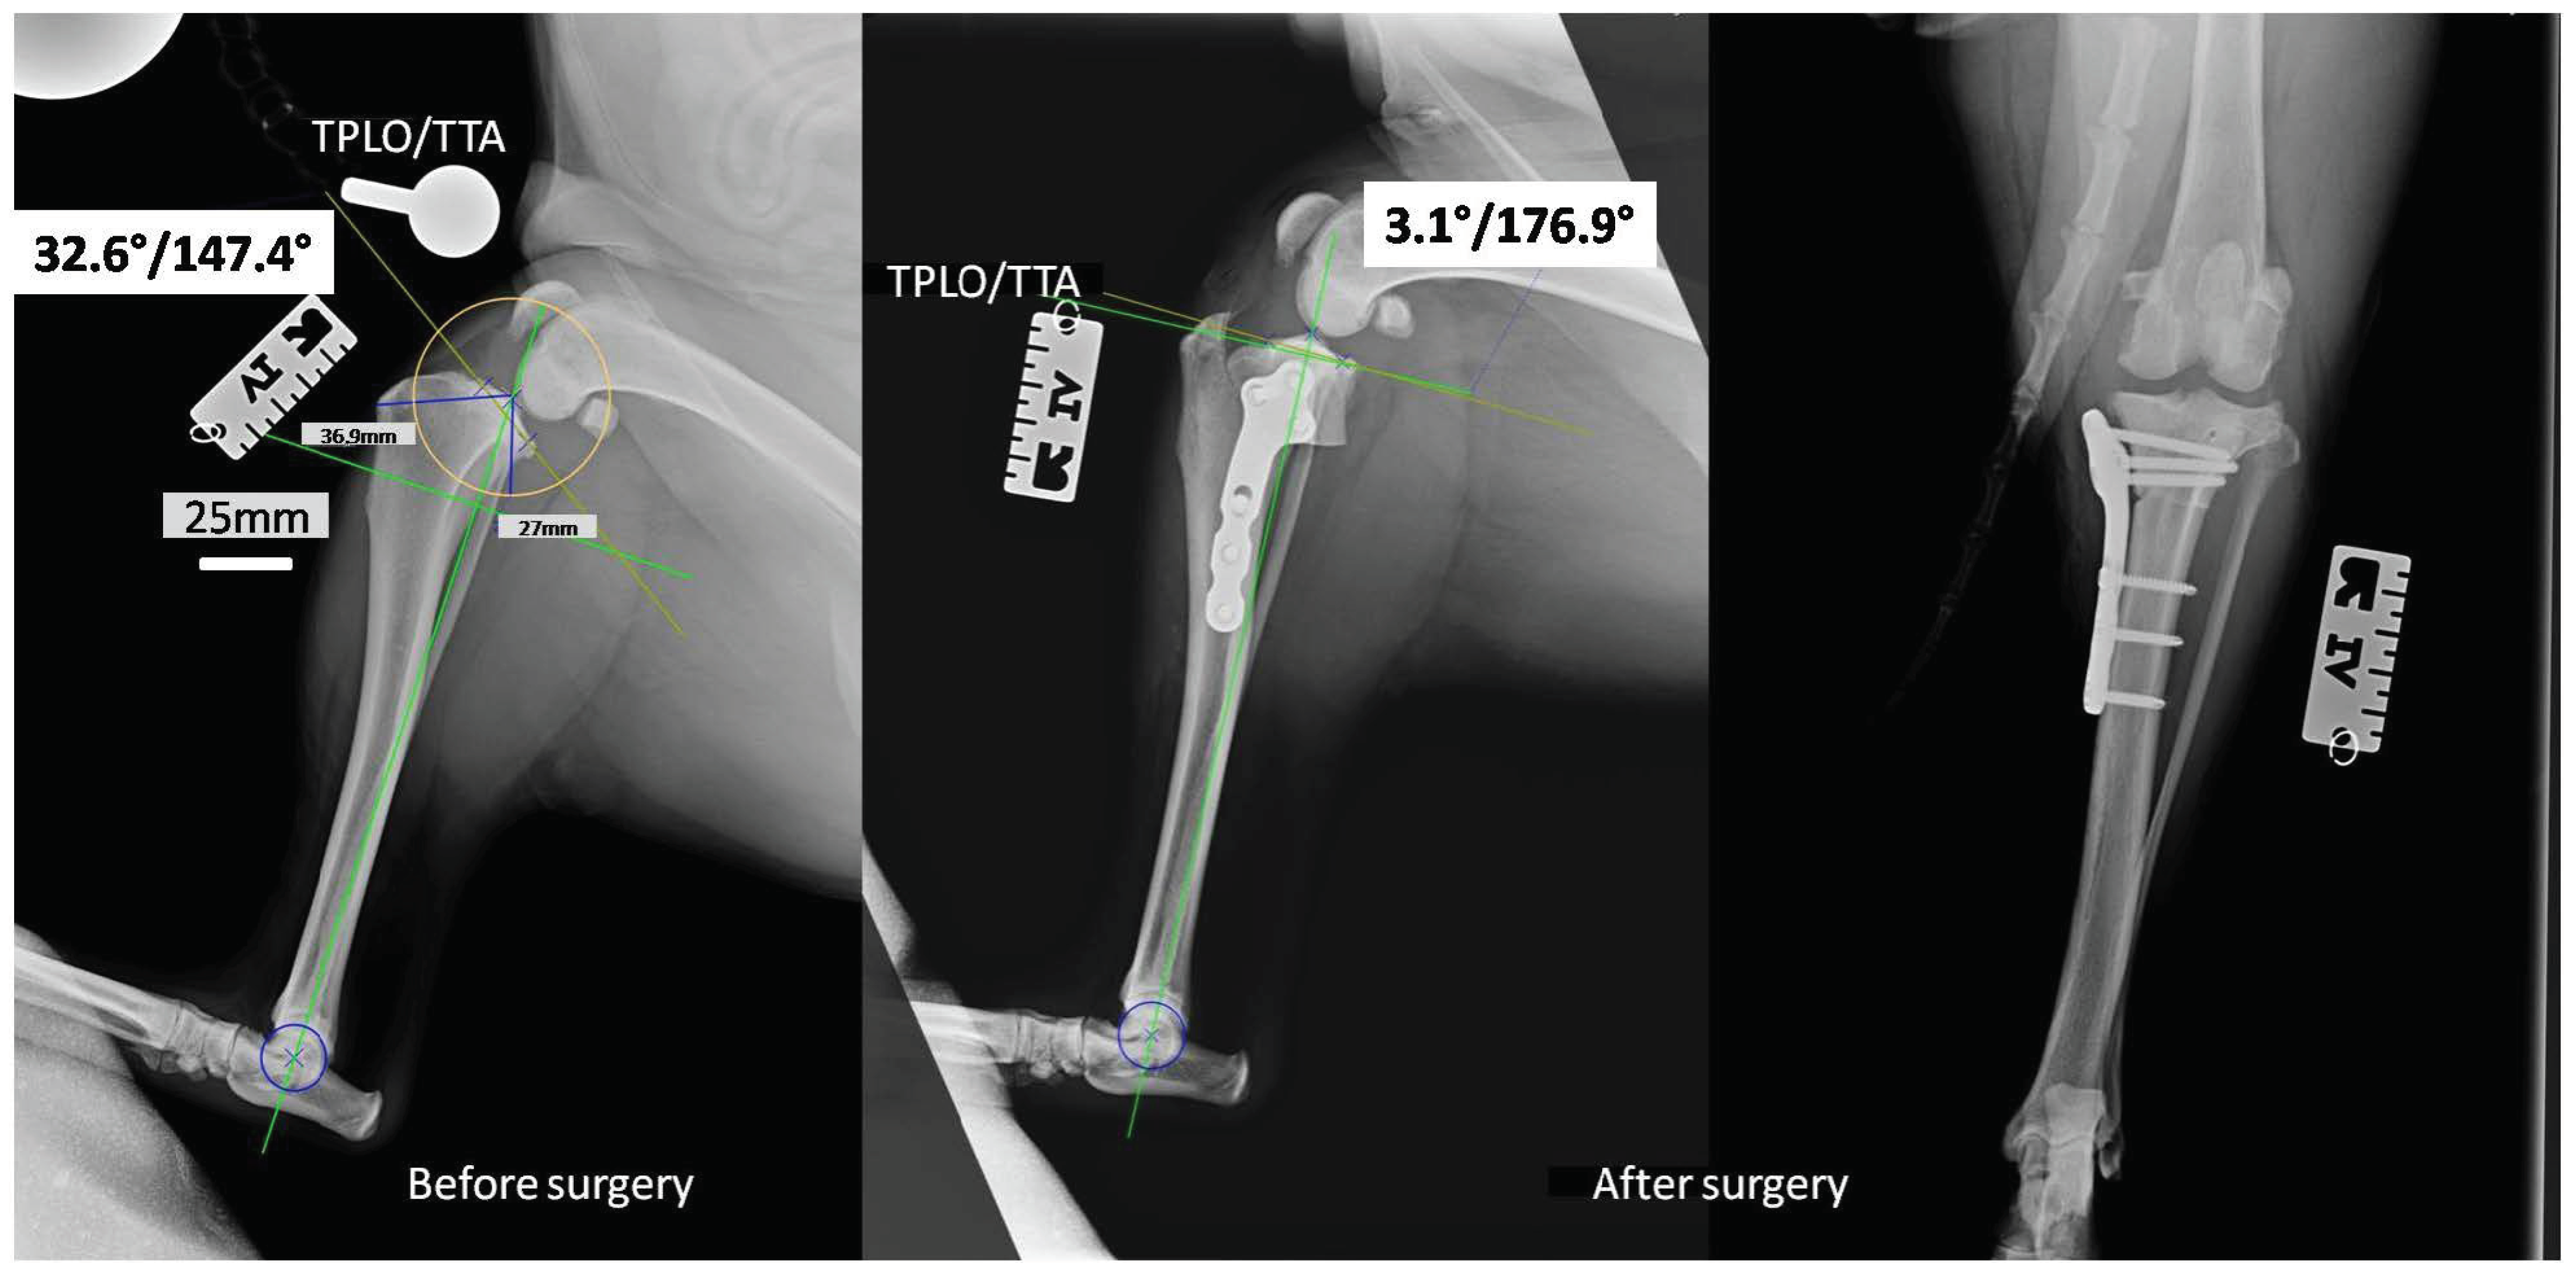

Taking into consideration the results collected from the bactericidal effectiveness and cell viability studies, we decided to use the implants covered with layers containing 0.5% AgNPs for in vivo studies on canine patients, the surgery using the TPLO implants modified with the layers containing silver nanoparticles. The in vivo studies were successful. None of the operated-on dogs revealed deviations in the postoperative period, and all the dogs returned to full fitness. In the X-ray pictures taken before and after the operation, the tibial inclination angle and tibial plateau angle (TPA) were below 5°, with an average of 3.1° (Figure 5). Such parameters complied with the general treatment standards and ensured the correct position of the plate and bolts. They represented the optimal angle of tibial plateau rotation providing joint stability in cranial cruciate ligament-deficient stifles [29].

Figure 5.

The X-rays of the stifle joint obtained for a representative dog before (horizontal) and immediately after the dog TPLO of a ruptured CrCL (horizontal and vertical).